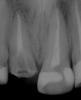

Ico Опубликовано 22 декабря, 2010 Поделиться Опубликовано 22 декабря, 2010 Для обработки каналов пользуюсь протейперами,для обтурации дают только стандартную и конусную гутту(04 и 06) и АН+.Плотно по объёму обтурировать иногда не получается-боюсь продавить силер,т.к. за пафы "ругают".Апексы стараюсь не ломать,силером только стенки обмазываю.Хочется ещё и дельту максимально закрыть.Знаю,что необходимо трёхмерное пломбирование,но пока вопрос о приобретении такой системы в клинику остаётся открытым.Доктора,посоветуйте,пожалуйста,как можно наиболие грамотно "залатералить" канал,разработаный протейпером?Попробуите сделать ап.упор фаилами и латеральте на здоровье.Апекс зондироавть только 10 - 15 а протеипер S2 ,F1 может апекс раскрыть поэтому доводите его на 1мм до апекса остальное делаите Н и К фаилами.Конусную гутту хорошо латералить не получится,она плотнее и под вертикалку нужна,кстати она и дороже обычнои гутты.Насчет пафов не знаю у меня они случаются иногда.семерка- до апексов на 0.5 фаил 30 дистальныи не помню но нобольше. http://s003.radikal.ru/i204/1012/c9/37316d43c891.jpgЗдесь мезиальные 30,дистальныи 35.http://i040.radikal.ru/1012/d4/c964ae3700cd.jpgПафы пошли 0,5 до апекса 45 фаил.http://s007.radikal.ru/i300/1012/b7/c1ae61d83293.jpgздесь 35 фаил.http://i045.radikal.ru/1012/11/05e37b25844e.jpghttp://i070.radikal.ru/1012/ac/e4cf942fa4a8.jpgПримерно так получается.Что дают тем работаем. Ссылка на комментарий

ger_berra Опубликовано 22 декабря, 2010 Автор Поделиться Опубликовано 22 декабря, 2010 Да МЕТА самая простоая и недорогаяПонятно.Есть такая.А мои снимки зацените,а то самооценочка хромает.Только,плиз,ничем не кидайтесь(тапками,помидорами,яйцами и т.п.),что без кофера.Каюсь,уже заказала набор.После 3-х недель с метапексом.Гранулирующий переодонтит 21Он же на метапексе.Прошло 3 месяца,постоянная обтурация АН+ гуттой(латералка) Ссылка на комментарий